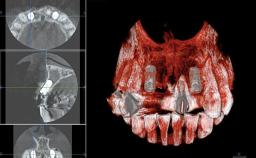

Replacement of Two Central Incisors and One Lateral Incisor with a Fixed Dental Prosthesis on Two Bone-Level Implants

A 38-year-old woman presented with an esthetically unacceptable fixed partial denture replacing teeth 11, 21, 22. She had lost these teeth due to trauma when she was a child. The patient was not in pain but very concerned based on her previous experience that dental treatments had never satisfied her esthetic expectations. She was in good general health and reported no regular medications. No periodontal disease was noted despite the fact that the buccal flange of the prosthesis impeded cleaning of the tooth abutments. The patient did not smoke and complied with home maintenance requirements, as evidenced by her good oral hygiene status.

Bone Volume | Deficient horizontally, requiring prior grafting |

Esthetic Risk | High |